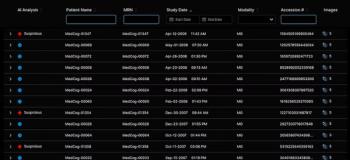

An emerging artificial intelligence (AI) software reportedly detected liver metastases in 53.7 percent of cases involving missed findings by radiologists.

Artificial intelligence (AI) diagnosed liver metastases overlooked by radiologists on abdominal computed tomography (CT) in more than half of the cases, according to newly published research.

The researchers found that the AI software concurred with radiologist findings in 92.7 percent of cases involving detected liver metastases and detected liver metastases in 53.7 percent of cases in which liver metastases were overlooked by radiologists. The AI software had an 0.48 average of false positives per patient, according to the study.

“Although this software version does not classify the detected lesions, our results have indicated its potential in reducing the number of overlooked liver metastases and providing reference information to the investigating radiologists,” wrote Yuji Nakamoto, M.D., Ph.D., a professor in the Department of Diagnostic Imaging and Nuclear Medicine at the Kyoto University Graduate School of Medicine in Japan, and colleagues.

Overall, the study authors noted that the AI software demonstrated per-lesion sensitivity rates of 70.1 percent for all liver lesions, 70.8 percent for liver metastases and 55 percent for liver metastases overlooked by radiologists.

Nakamoto and colleagues pointed out that the AI software failed to detect 16 percent of liver metastases diagnosed by radiologists and specifically noted a failure to diagnose liver metastases that contacted large hepatic veins.

“This leads us to believe that lesions surrounded by the liver parenchyma may be easier for the (AI) software to detect than those that are not,” suggested Nakamoto and colleagues. “Therefore, the software would not replace the radiologists. Instead, the software should be used in conjunction with the radiologists’ clinical interpretation.”

The study authors noted that the Care Advisor for Liver AI software is currently pending review by the Food and Drug Administration (FDA).